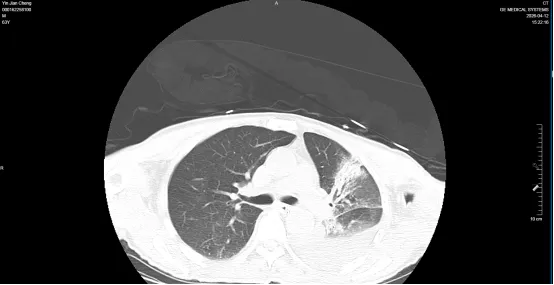

4月12日复查肺部CT

入科后,在科主任孟磊牵头指导下,团队迅速制定个体化诊疗方案,立即予气管插管有创机械通气,累计机械通气9天。严重休克,血管活性药物维持血压,纤支镜吸痰肺泡灌洗术及肺复张术,且留取肺泡灌洗液NGS监测,次日肺泡灌洗液NGS示:鹦鹉热衣原体,据结果立即调整抗感染方案,俯卧位通气7天。面对罕见病原体与多器官衰竭双重难关,重症医学科团队精准研判,制定个体化救治方案:实施肺保护性通气策略、精细化俯卧位通气管理、针对性抗感染、器官支持与抗炎护脏综合治疗,24小时不间断监护,全力守护生命防线。

历经日夜坚守与科学施治,患者感染逐步控制,氧合显著改善,器官功能稳步恢复,成功脱离呼吸机、脱离危险,循序渐进,无创通气更换为经鼻高流量氧疗,每日管床医生与护士协助患者床旁坐位,吹气球,并鼓励患者有信心,有毅力,赶走病魔,适宜锻炼,促进康复。呼吸及循环稳定后,患者转危为安,转普通病房继续巩固治疗。